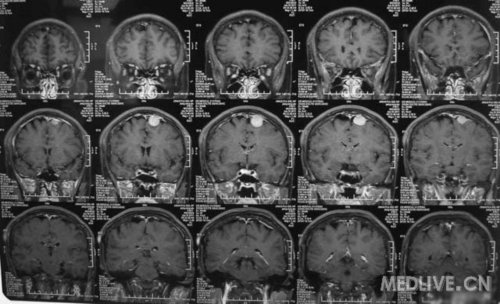

患者女,56岁,因右侧肢体活动不利2天于2011-06-15入院。查体:神志清,精神可,右侧肢体肌力4级,余无阳性体征。CT示左额叶占位,脑膜瘤可能性大。MRI示左额镰旁脑膜瘤,脑干左半亚急性梗塞。给予活血、神经营养、对症治疗,现一般情况好。请高手指点,何时手术切除脑膜瘤好啊?